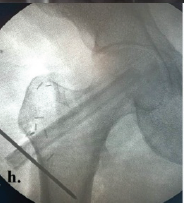

Outcomes of Internal Fixation in Proximal Humerus Head Split Fractures in Young Adults – How Often Is It Missed and Can We Really Afford to Do So

Kaustav Mukherjee , Tarun Prashanth , Dorai Kumar Raja , Mohan Kumar